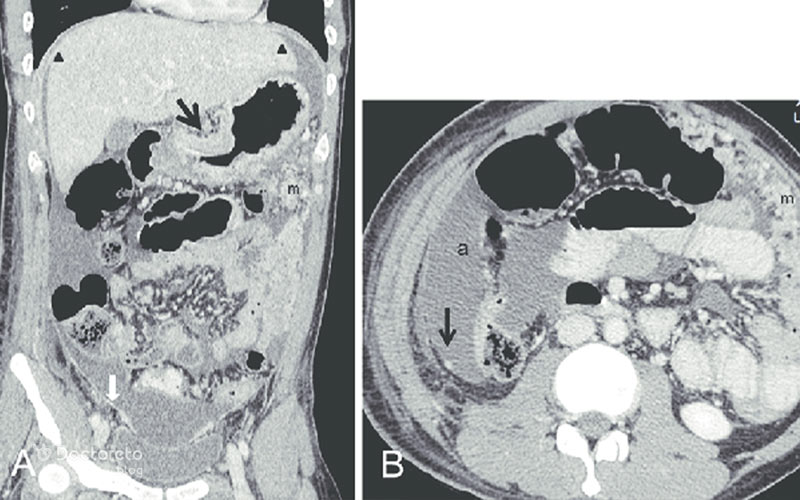

عکس سی تی اسکن سرطان معده بدخیم

در ادامه تصویر سیتیاسکن مربوط به سرطان معده بدخیم را مشاهده میکنید. سیتیاسکن به پزشک اجازه میدهد تا محل، اندازه و گسترش تومور را در معده و غدد لنفاوی اطراف و ارگانهای مجاور ارزیابی کند، که برای برنامهریزی درمان بسیار مهم است.